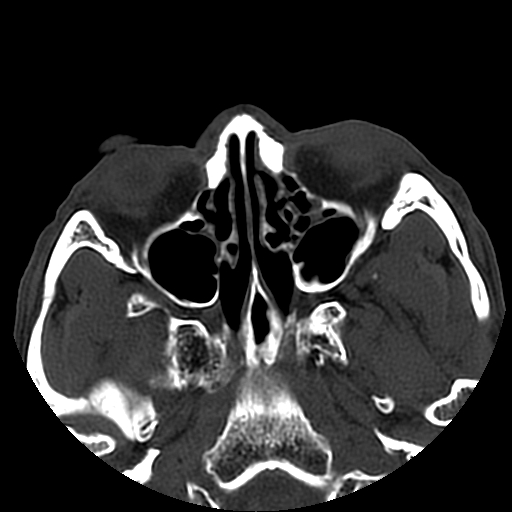

以下是引用liaoqiang在2008-7-16 21:15:00的发言:[br]右侧鼻骨骨折

以下是引用zxd95在2008-7-16 21:39:00的发言:[br]右侧上颌骨额突骨折。[br][br][br][br]